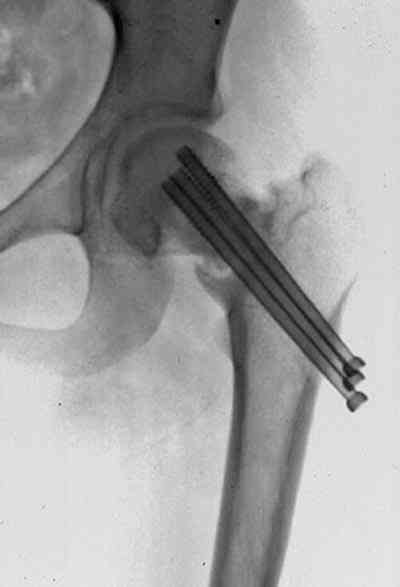

На снимках ложный сустав шейки бедра, несостоятельность фиксации. По положению шурупа можно предсказать ложный сустав, например, если screw backup за кортикальный слой около 15-20 мм, и также изменение угла от первоначального.

№2-3 типичная ошибка несоблюдения концепции параллельности шурупов, нарушение-фиксация поперечным допольнительным шурупом для приближения отломка в результате не сработало метод параллельных шурупов

№4 результат на КТ